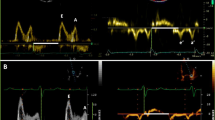

Impedance has been used in vascular biology to characterize the frequency dependent opposition the circulatory system presents to blood flow in response to a pulsatile pressure gradient. It has also been used to characterize diastolic function (DF) via the early, diastolic left ventricular (LV) pressure–flow relation. In a normal LV, early filling volume is accommodated primarily by wall-thinning and ascent of the mitral annulus relative to the spatially fixed apex (longitudinal chamber expansion). Simultaneously, the endocardial (transverse or short axis) dimension also increases while epicardial (transverse) external dimension remains essentially constant. To quantify these directional filling attributes, we compute longitudinal (Z L) and transverse (Z T) impedances during early rapid-filling (Doppler E-wave). Z L and Z T were calculated from 578 cardiac cycles of simultaneous transmitral flow and high fidelity LV pressure data in 17 subjects with normal LV function. Average Z L was 0.7 ± 0.4 mmHg s/cm4 and average Z T was 238 ± 316 mmHg s/cm2. Direct comparison, in the same units is achieved by computing Z T over the ≈10 cm2 cross-sectional area of LV (denoted ŽT) revealing that Z L is ≈34 times smaller than ŽT. This quantifies the physiologic preference for longitudinal LV volume accommodation. Lowest Z L and Z T values occurred in the first harmonic with monotonically increasing values with higher harmonics. We conclude that Z L and Z T characterize longitudinal and transverse chamber properties of DF and therefore, diastolic dysfunction can be viewed as a state of impedance mismatch.